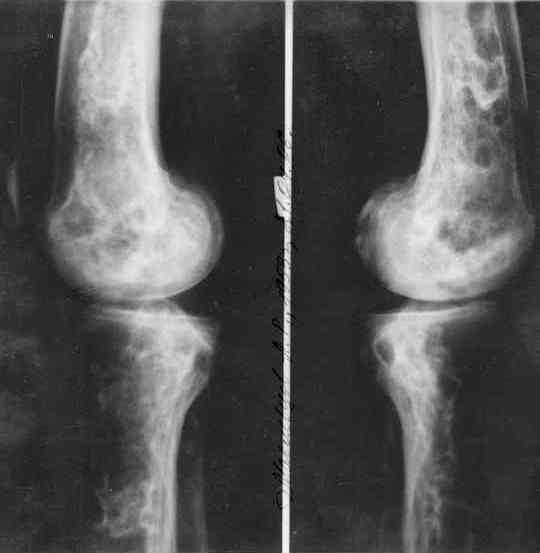

Уважаемый Константин Иванович! Полностью согласен с проф. Михайловым, данный случай не похож на мраморную болезнь, при которой имеется резкое, строго симметричное и генерализованное уплотнение костной ткани (остеопетроз), и кость оказывается построенной преимущественно из гомогенного компактного костного вещества. Для примера привожу случай из архива нашего института (бедренные, плечевые кости и таз, рис 1,2,3)

Изменения структуры костей у Вашего пациента больше похожи на полиоссальную форму фиброзной дисплазии или болезнь Педжета, возможены также инфаркты костного мозга б.берцовых костей. К сожалению, качество снимка не очень хорошее, непонятно, сохранен ли кортикальный слой б.берцовых костей по передней поверхности.

Для примера привожу случай из архива американской ассоциации рентгенологов (ACR) - развитие злокачественной фиброзной гистиоцитомы на левой б.берцовой кости у пациента с множественными инфарктами костного мозга (рис 4,5 - левая, рис 6 - правая)